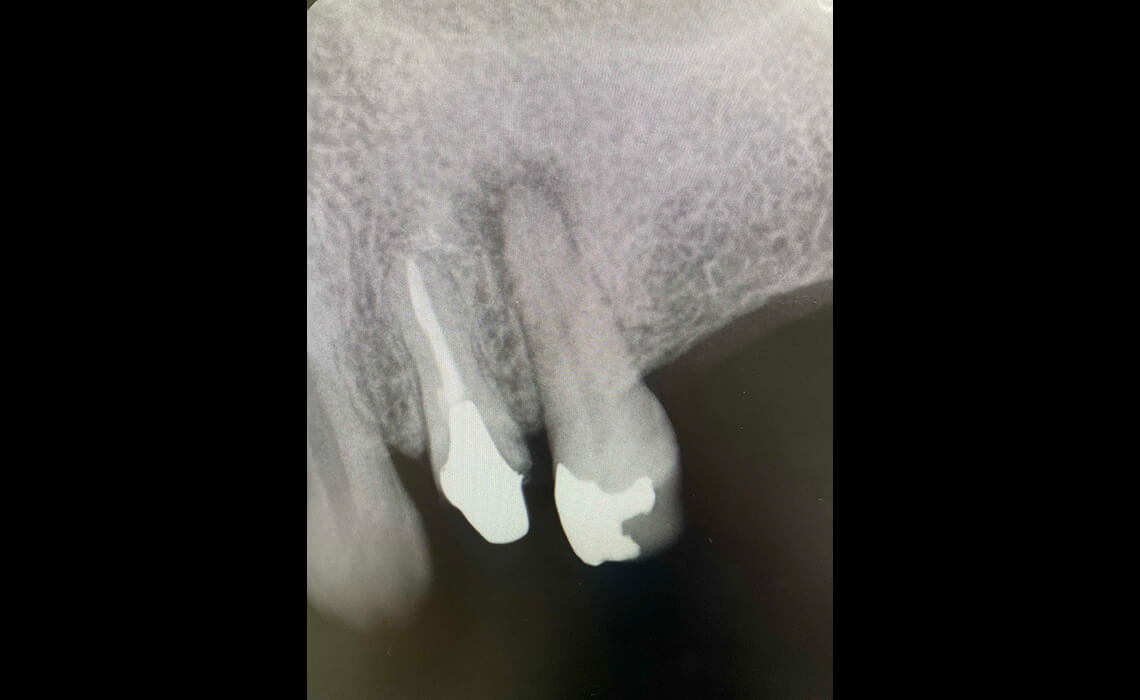

まずはカウンセリングと診査を行います。デジタルレントゲンやCTで歯の内部や根管の形を正確に把握し、治療計画を立てます。

CASE